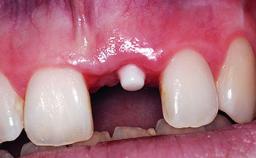

A 49-year-old female patient was referred for implant therapy to replace the upper right central incisor (tooth 11). The tooth had been assessed by an endodontist who diagnosed a vertical fracture of the root. The tooth had a hopeless prognosis and needed to be extracted. The patient was healthy and was not taking any medications. She was allergic to penicillin. The patient had high esthetic demands but her expectations were realistic. The extraoral examination revealed no facial asymmetries. The right temporomandibular joint demonstrated an opening click but was otherwise asymptomatic. The lip line was high with a significant gingival display.

| Placement Protocol | Early or late implant placement |

| Bone Volume | Deficient vertically or deficient vertically AND horizontally |